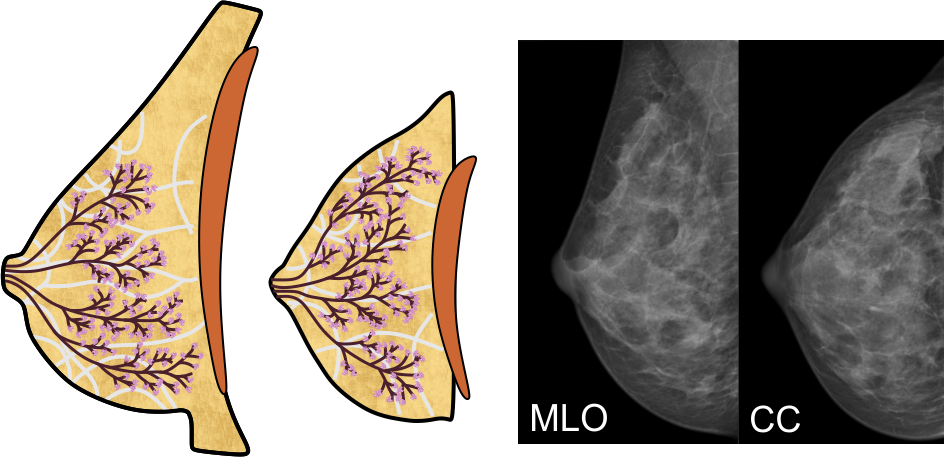

Die weibliche Brust

Die weibliche Brust besteht in Hauptsache aus den vier Komponenten Fettgewebe, Bindegewebe, und den Milchgängen und Milchdrüsenläppchen, die zusammen die Brustdrüse bilden:

Das Fettgewebe gibt der Brust ihre Form, das Bindegewebe durchzieht die Brust in gewölbten, fächerartigen Bahnen und verleiht ihr Stabilität. Die Milchgänge leiten die Milch zur Brustwarze, und in den Drüsenläppchen wird die Milch gebildet; die rotbraune Fläche in den obigen Abbildungen symbolisiert den Brustmuskel.

Aufbau der Brust

Die vier oben genannten Gewebearten sind in ihren Anteilen in jeder Brust individuell angelegt. Die meisten Frauen haben eine ausgewogene Verteilung, bei manchen kann jedoch eine bestimmte Gewebeart überwiegen. Dazu verändert sich die Brust mit zunehmendem Alter, die Milchgänge und das Bindegewebe werden vor allem nach dem Wechsel dünner, die 'Blätter' des Baums 'verwelken' - die Drüsenläppchen schrumpfen also, und der Fettgewebeanteil wird größer. Üblicherweise entwickeln sich diese Veränderungen von innen nach außen, und von unten nach oben.